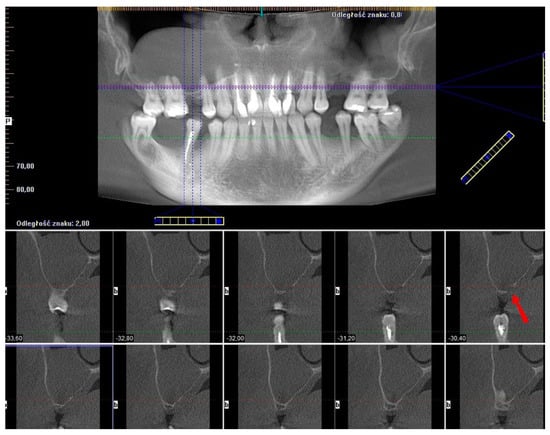

2.3. Case 3—Final Version Upgraded with a Surgical Guide for the Window Osteotomy

The last presented case (by A.N.) is the variation of the final version of the CET. It shows effectiveness even against a large (45.44 mm maximum diameter) retention cyst (Figure 14). Moreover, the sinus lift part was guided by a surgical guide (Figure 15), which indicated the ideal position of the window. The decision to conduct the surgery with a guide was dictated by the potential risk of the nonoptimal location of the osteotomy due to a lack of teeth or other reference points in that area. Lastly, this case presented another difficulty in the form of past oroantral communication (OAC) (Figure 16), which, from the very beginning, sentenced the surgeon to deal with another perforation of the Schneiderian membrane.

Figure 8. Croco Eye Technique—final version. Screenshot of the pre-op CBCT scans with a visible radiopaque lesion in the right maxillary sinus, insufficient alveolar ridge height, and noncontinuous bone of the sinus floor due to past oroantral communication (OAC) (red arrow).